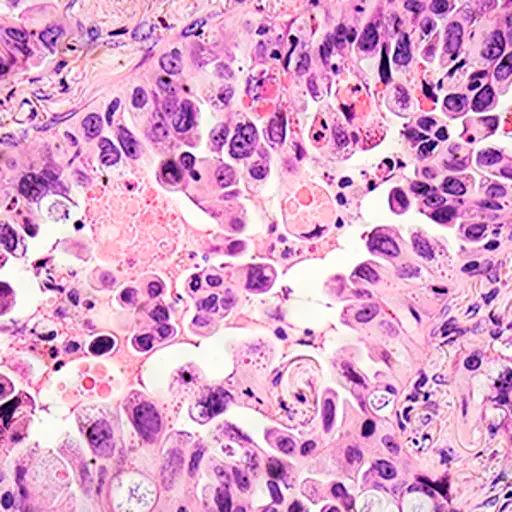

腺癌

腺癌是非小细胞肺癌的三种主要亚型之一,是生长在器官内膜的癌症,通常生长在产生分泌物的细胞中。腺癌是肺癌中最常见的一种,在所有肺癌患者中有超过50%的人被诊断为腺癌。它生长在肺泡的内壁,生长在产生粘液的细胞里。

大细胞癌

最不常见的是NSCLC的三个主要亚型,大细胞癌的肺部内衬在肺部的内衬里;大约10%的NSCLC诊断被称为大细胞。它的特征在于它在通常大于大多数肺细胞的细胞中生长。

鳞状细胞癌

其中非小细胞肺癌,鳞状细胞癌(又称表皮样癌)的三个主要亚型的约占25所有肺癌的百分比。它生长在衬里内表面的小型平坦鳞状细胞中。